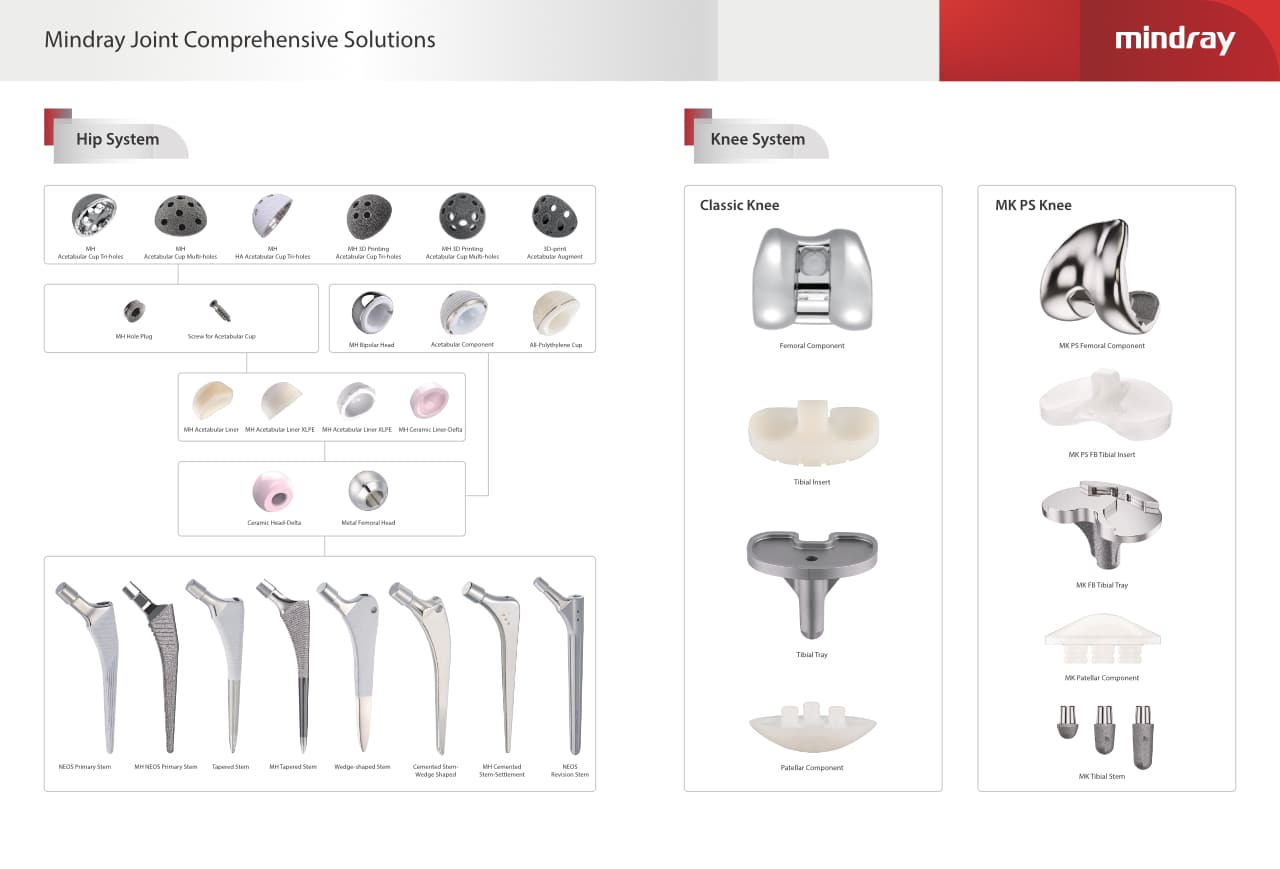

Reemplazo articular (Artroplastia)